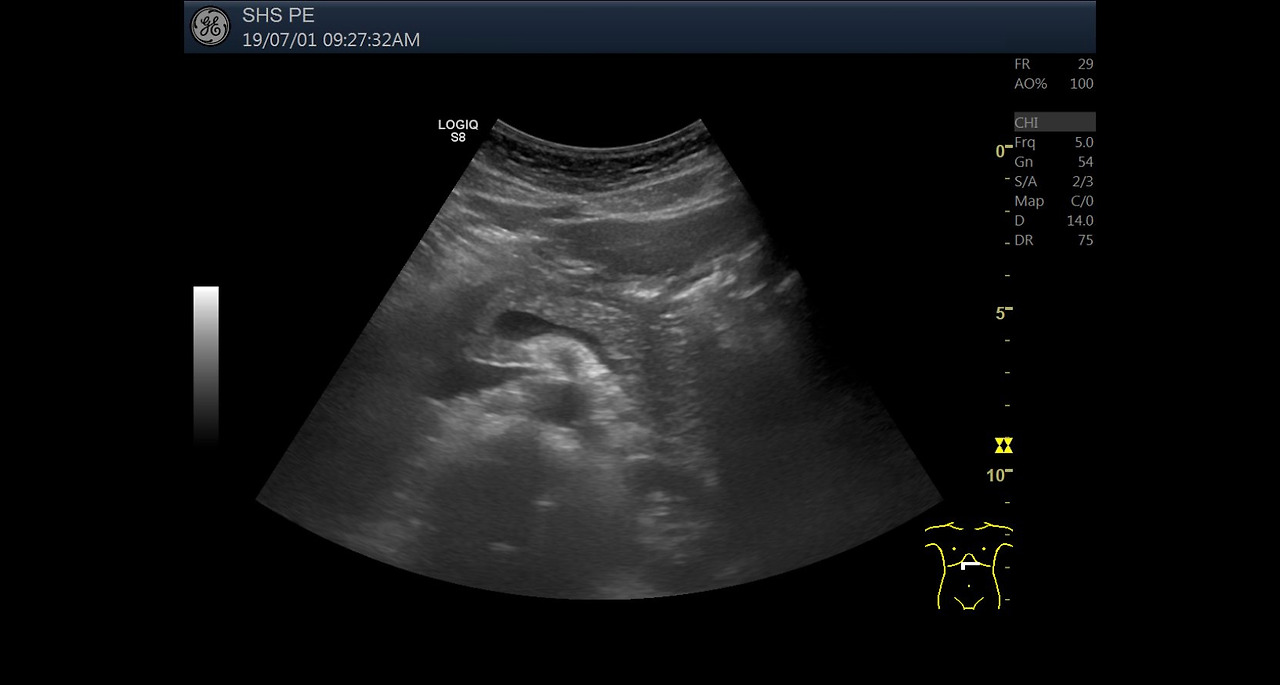

초기 증상이 애매하고 흔한 소화기 증상과 유사하기 때문에 크론병은 진단이 늦어지는 경우가 많습니다. 그러나 진단이 지연될수록 염증이 깊어지고 장 손상이 누적되어 수술적 치료가 필요한 상황으로 이어질 가능성이 높아집니다. 따라서 증상이 반복되거나 장기간 지속된다면 단순 증상 완화에만 의존하지 말고 전문적인 평가를 받는 것이 필요합니다.

크론병은 급성으로 끝나는 질환이 아니라, 증상이 좋아지는 관해기와 다시 악화되는 재발기를 반복하는 것이 일반적입니다. 관해기에는 비교적 일상생활이 가능하지만, 재발기에는 증상이 급격히 악화되어 입원 치료가 필요한 경우도 적지 않습니다. 또한 질환 기간이 길어질수록 장 협착이나 누공 같은 합병증 위험이 증가하기 때문에 조기 진단과 지속적인 관리가 매우 중요합니다.